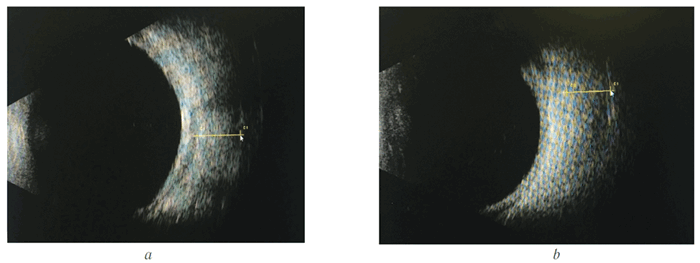

Через 4 месяца после начала лечения острота зрения восстановилась до 1,0 с коррекцией, ВГД остаётся компенсированным (18 мм рт. ст.) без медикаментозной коррекции, остаточный экзо фтальм — 5 мм (рис. 5). При контрольной эхографии орбит нижняя и внутренняя прямая мышцы уменьшены в объёме, в поперечнике — практически на 1 мм (рис. 6).

Рис. 6. Эхограммы орбиты (по окончании лечения): a — нижняя прямая мышца, 5,6 мм; b — внутренняя прямая мышца, 5,46 мм

Fig. 6. Echograms of orbits after treatment: a — lower rectus, 5.6 mm; b — internal rectus, 5.46 mm